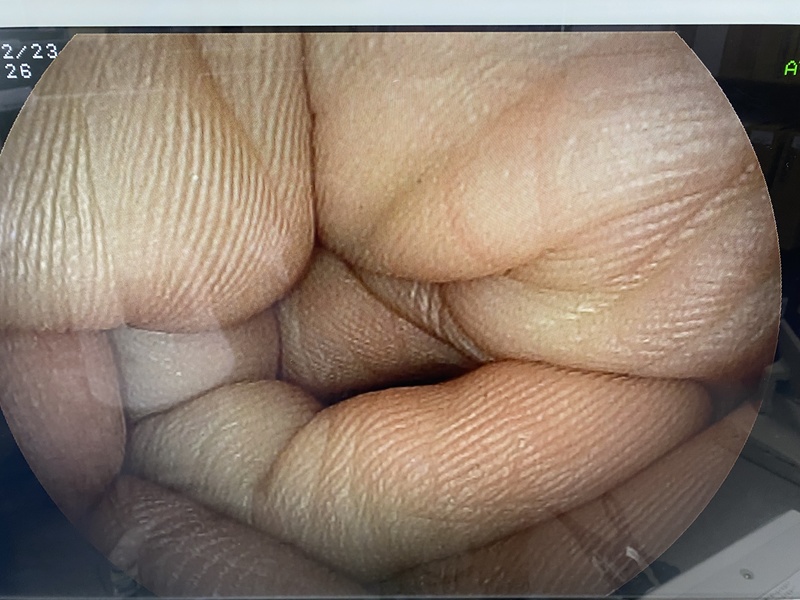

- detail Video Gastroscope / 17162 / EG-3000FP